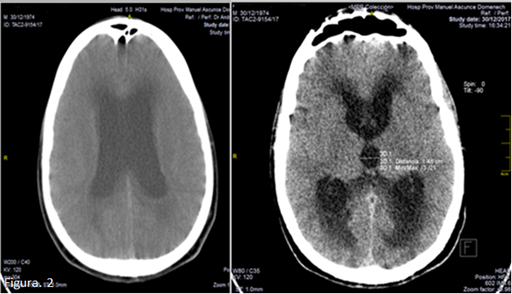

Al mes de operado fue admitido en emergencia porque comenzó con cefalea, confusión mental y papiledema sin fiebre. Al examen físico se halló reflejo plantar extensor bilateral y paraparesia flácida sin nivel sensitivo, trastornos esfinterianos y rigidez nucal. Se realizó en ese momento tomografía axial computada (TAC) de cráneo simple donde se observa una dilatación metaventricular con edema periventricular y ensanchamiento del 3er ventrículo de 14mm, índice de Evans 0,39; lo que se interpretó como una hidrocefalia aguda y se colocó un sistema de derivación ventrículo peritoneal (Figura 2).